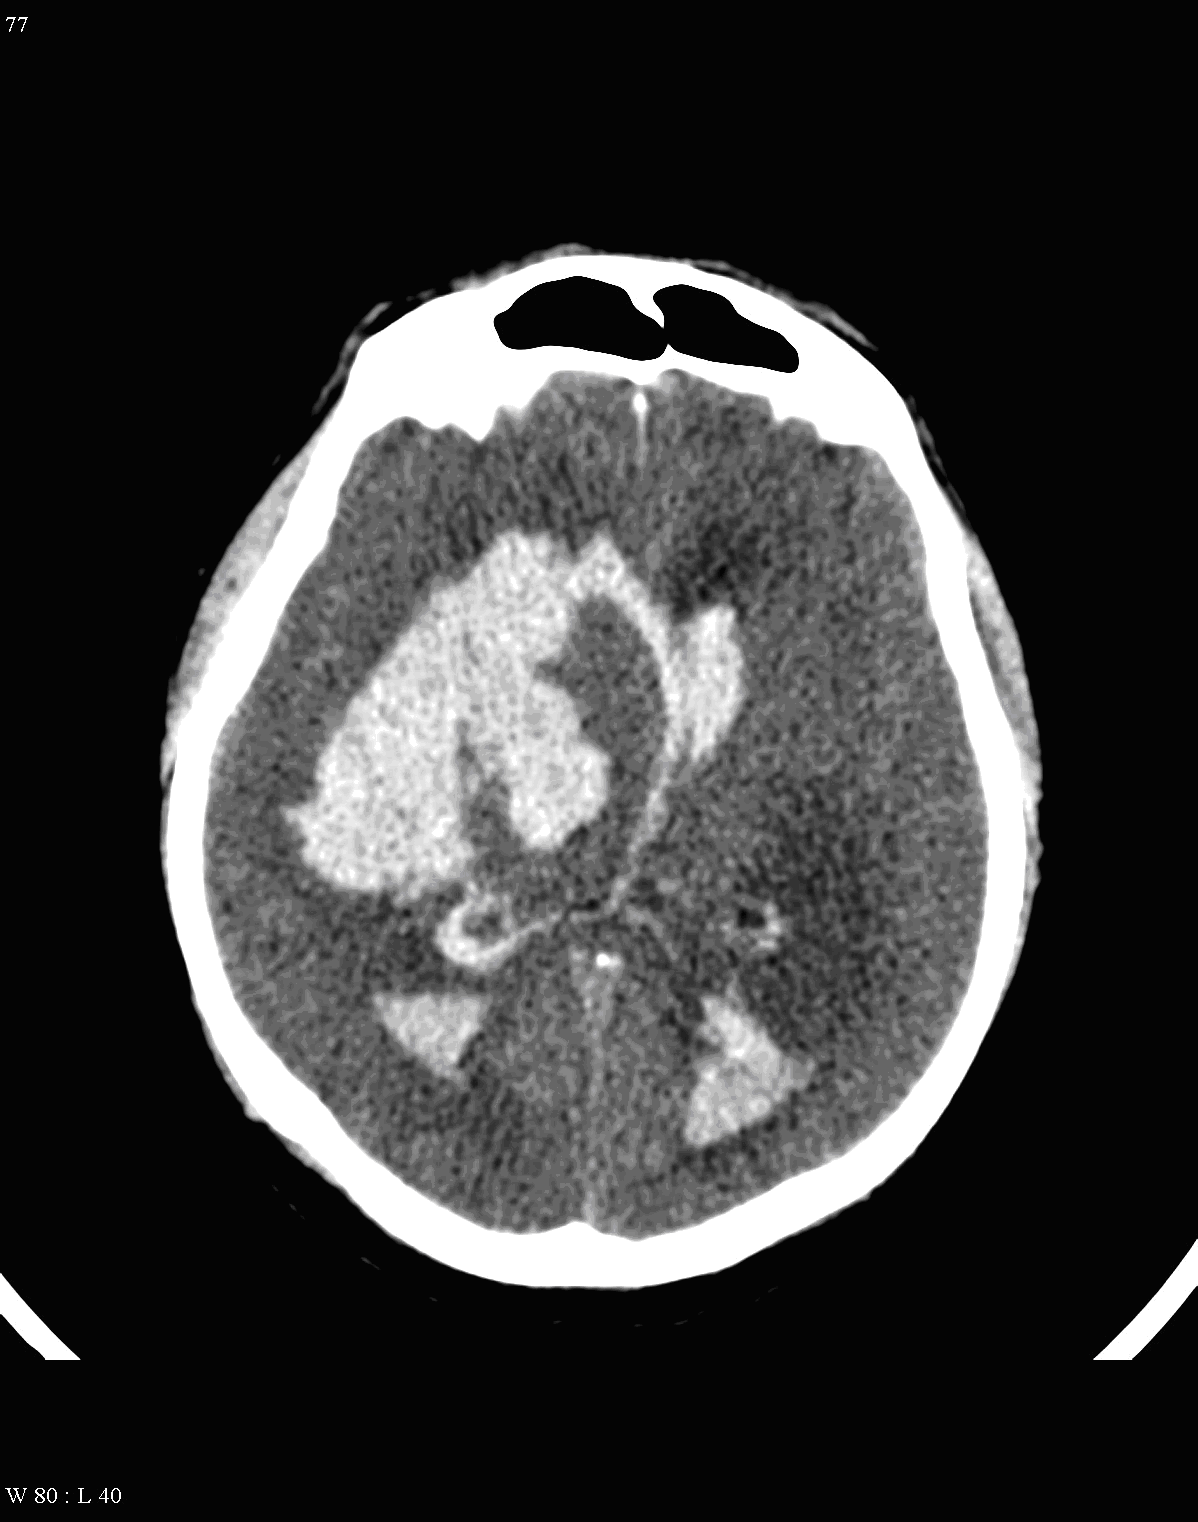

Although, subarachnoid hemorrhage (SAH) is most often caused by the rupture of a berry aneurysm, arteriovenous malformation (AVM) and trauma can also lead to it. SAH is typically located at the basal subarachnoid spaces, which then propagates along the lateral fissures or it fills up the interhemispheric fissure till the convexities. The main collection of the blood is usually indicative of the source of origin. In cases of parenchymal spread the mechanism, whether it broke in, or it broke out from the parenchyma could represent a differential diagnostic challenge. When accompanied by brain edema, the consequent herniation can result in parenchymal infarcts as well.

CT angiography examination is usually advisory in order to confirm the site of the bleeding. It is also effective when a hemorrhagic tumor is in the differentials, although complete differentiation might only be achieved by follow-up examinations. CTA is also essential in the diagnostics of multiple aneurysms (which are prevalent in 20-30% of the cases based on autopsy reports.) In case of a subarachnoid hemorrhage the consequently developing hydrocephalus and its degree might only be detected on follow-up CT examinations. It is very important to note that an initial brain aneurysm rupture might be followed by a second one within the first 7 – 10 days and the resulting vasospasm carries a much higher risk of mortality than the one at the time of the first SAH. This is why the scrutonius review of the acute diagnostic imaging is essential and it plays a fundamental role in patient treatment. Open brain surgery of the aneurysm (clipping) has been replaced by catheter angiography (DSA) nowadays. The aneurysm is either filled up with thrombogenic coils through its neck or recently bypassing stents are inserted to exclude the aneurysm from the cerebral circulation.

The remaining (5%) of the patients can suffer spontaneous subarachnoid hemorrhage that most often results from brain aneurysm (on the branches of Circle of Willis) or from vascular malformations.

Bleeding usually originates from saccular “berry” aneurysms (on the branches of the Circle of Willis). Aneurysm rupture besides subarachnoid hemorrhage can also cause intraparenchymal bleeding when it breaks into the parenchyma.